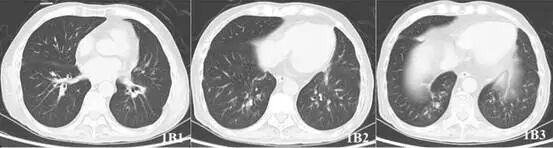

气管镜提示:双肺各叶段大量黄脓痰,质粘拉丝,右侧为著;右主吻合口处可见大量黄褐色假膜附着,右上及中间段开口处可见大量黄白色假膜覆盖,无法完全吸除;左主吻合口处可见少量黄色附着物(图2A1-2)。综合考虑不除外曲霉菌感染复发可能性。此外,患者白细胞、淋巴细胞计数均下降,FK506浓度偏高,遂停用吗替麦考酚钠,将他克莫司减量并多次留取病原学,等待结果回报。

图2A1-2:可见大量黄色粘稠分泌物及黄白色假膜覆盖,无法完全吸除

2018年7月20日,抗真菌治疗49天后,停用米卡芬净。2018年8月30日复查CT(图1B1-3)及气管镜(图2B1-2)基本正常。后多次复查BALF病原学无帚霉证据。患者于2018年9月5日停用特比萘芬及伯沙康唑,共计118天。目前患者术后近4年,规律随访中。

图2B1-2. 2018-8-30复查气管镜:粘膜轻度充血,少量分泌物,前次黄白色假膜消失。